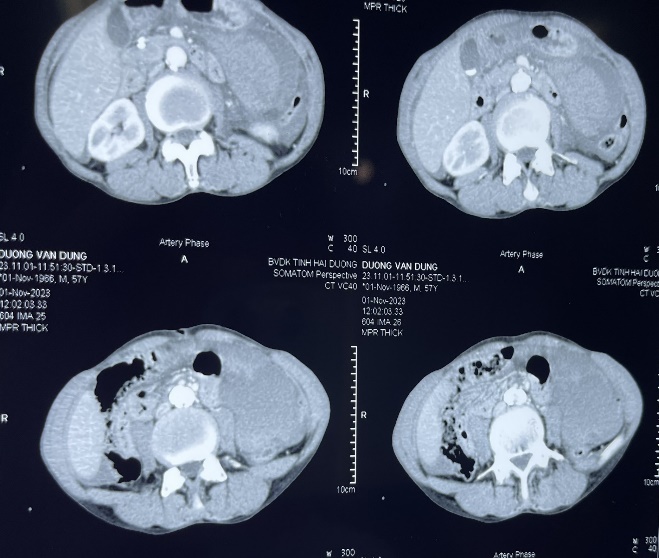

NHÂN MỘT TRƯỜNG HỢP CHẤN THƯƠNG TỤY

07/11/2023 (GMT+7)

Chấn thương tụy là một chấn thương hiếm gặp nhưng có khả năng gây tử vong cao và rất khó chẩn đoán. Các phương pháp hình ảnh thông thường hay bỏ sót những tổn thương tinh tế liên quan đến chấn thương tuyến tụy.